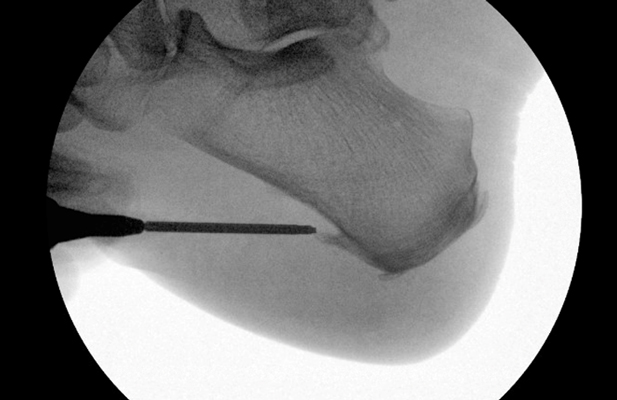

TOTAL ANKLE REPLACEMENT :: ORIF CALCANEUS :: ORIF ANKLE FRACTURE DISLOCATION :: COMPLEX BUNION AND LESSER TOE CORRECTION :: TALUS FRACTURE -1 :: TALUS FRACTURE -2 :: LISFRANC REPAIR :: COMPLEX TRIPLE ARTHRODESIS 1 :: COMPLEX TRIPLE ARTHRODESIS 2 :: MINIMALLY INVASIVE BUNION REPAIR 1 :: MINIMALLY INVASIVE BUNION REPAIR 2 :: ARTHROSCOPIC CARTILAGE REPAIR :: TENEX SPUR DEBRIDEMENT :: Haglunds Debridement and Achilles Repair